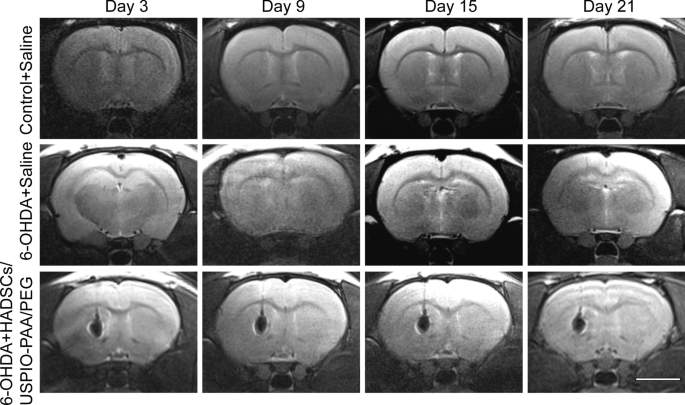

HADSCs labeled with USPIO-PAA/PEG NPs were transplanted into the left striatum of PD rat model by stereotactic injection. As shown in Fig. 5, we observed a clear MRI signal in the left striatum 3 days after the HADSC transplantation, indicating a proper in vivo tracing of the transplanted cells. A dynamic observation on D3, D9, D15 and D21 after transplantation showed that the transplanted cells with NP labeling could be clearly traced up to 3 weeks, and the MRI signals did not show obvious reduction during the process. These results indicate that the synthesized nanoparticles have good potential for the in vivo tracing of the transplanted cells.

Representative MRI images of the brains at 3 days, 9 days, 15 days and 21 days followed by transplantation with USPIO-PAA/PEG labeling HADSCs or saline. The MRI images of the corresponding controls, i.e. normal rats or PD rat model injected with saline, were shown in the 1st and 2nd rows, respectively. Note that compared to the negative signals in the control, the rat brains transplanted with USPIO-PAA/PEG-labeled HADSCs showed a constant and clear MRI signals up to 21 days. The bar represents 5 mm